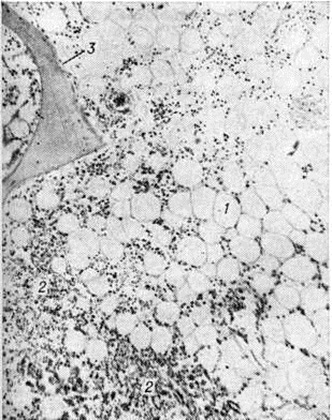

Рис. 1. Микропрепарат костного мозга при остром лимфобластном лейкозе: очаговый коагуляционный некроз ткани (1) на фоне лейкозной инфильтрации (2), в окружности некроза кровоизлияния, скопления макрофагов (3), рассасывание костной ткани с истончением костных балок (4). Окраска гематоксилин-эозином; × 80.

В костном мозге, по данным трепанобиопсии, на первых стадиях заболевания скопления бластных клеток являются очаговыми, в достаточном количестве обнаруживаются элементы деятельного костного мозга. Нередко наблюдаются острые расстройства кровообращения, участки гипоплазии, могут обнаруживаться некрозы. Прогрессирование заболевания характеризуется увеличением числа и размеров лейкозных разрастаний, их слиянием, а затем диффузной инфильтрацией ткани костного мозга. Количество нормальных кроветворных клеток заметно уменьшается. Часто имеется инфильтрация надкостницы, возможно распространение процесса в окружающие мягкие ткани. Развитие лейкозных разрастаний сопровождается выраженным рассасыванием костной ткани, преимущественно по типу гладкой резорбции. Очень редко в этом процессе принимают участие остеокласты. Вследствие частичного, а местами и полного рассасывания костных балок происходит значительное расширение костномозговых полостей, истончение, а в некоторых участках разрушение кортикального слоя. В раннем детском возрасте резкие изменения наблюдаются в зоне энхондрального окостенения. При острых Лейкозы редко отмечается очаговое новообразование атипичной костной ткани, богатой остеоидом, разрастание фиброзной ткани. Наряду с мелкими фокусами некроза иногда возникают обширные инфарктообразные коагуляционные некрозы, определяемые макроскопически в виде жёлто-белых сухих участков; в окружности наблюдаются кровоизлияния, возможно скопление макрофагов (рисунок 1). В области лейкозных разрастаний нередко обнаруживается истончение и частичный распад ретикулярных волокон. Описаны наблюдения с очаговым или диффузным миелофиброзом, который чаще выявляется при миелобластном Лейкозы. В таких случаях при пункции обычно не удаётся получить костный мозг и для установления диагноза необходимо исследование материала трепанобиопсии.

Лейкозная инфильтрация ткани селезёнки и лимфатических, узлов сопровождается уменьшением размеров (рисунок 2) и числа фолликулов вплоть до полного их исчезновения. В селезёнке часто наблюдается инфильтрация трабекул с разволокнением стенок трабекулярных сосудов, с деформацией и сужением их просвета, имеются поля кровоизлияний. В лимфатических, узлах вначале возникают очаговые инфильтраты, которые по мере прогрессирования болезни увеличиваются в размерах, и поражение становится диффузным.